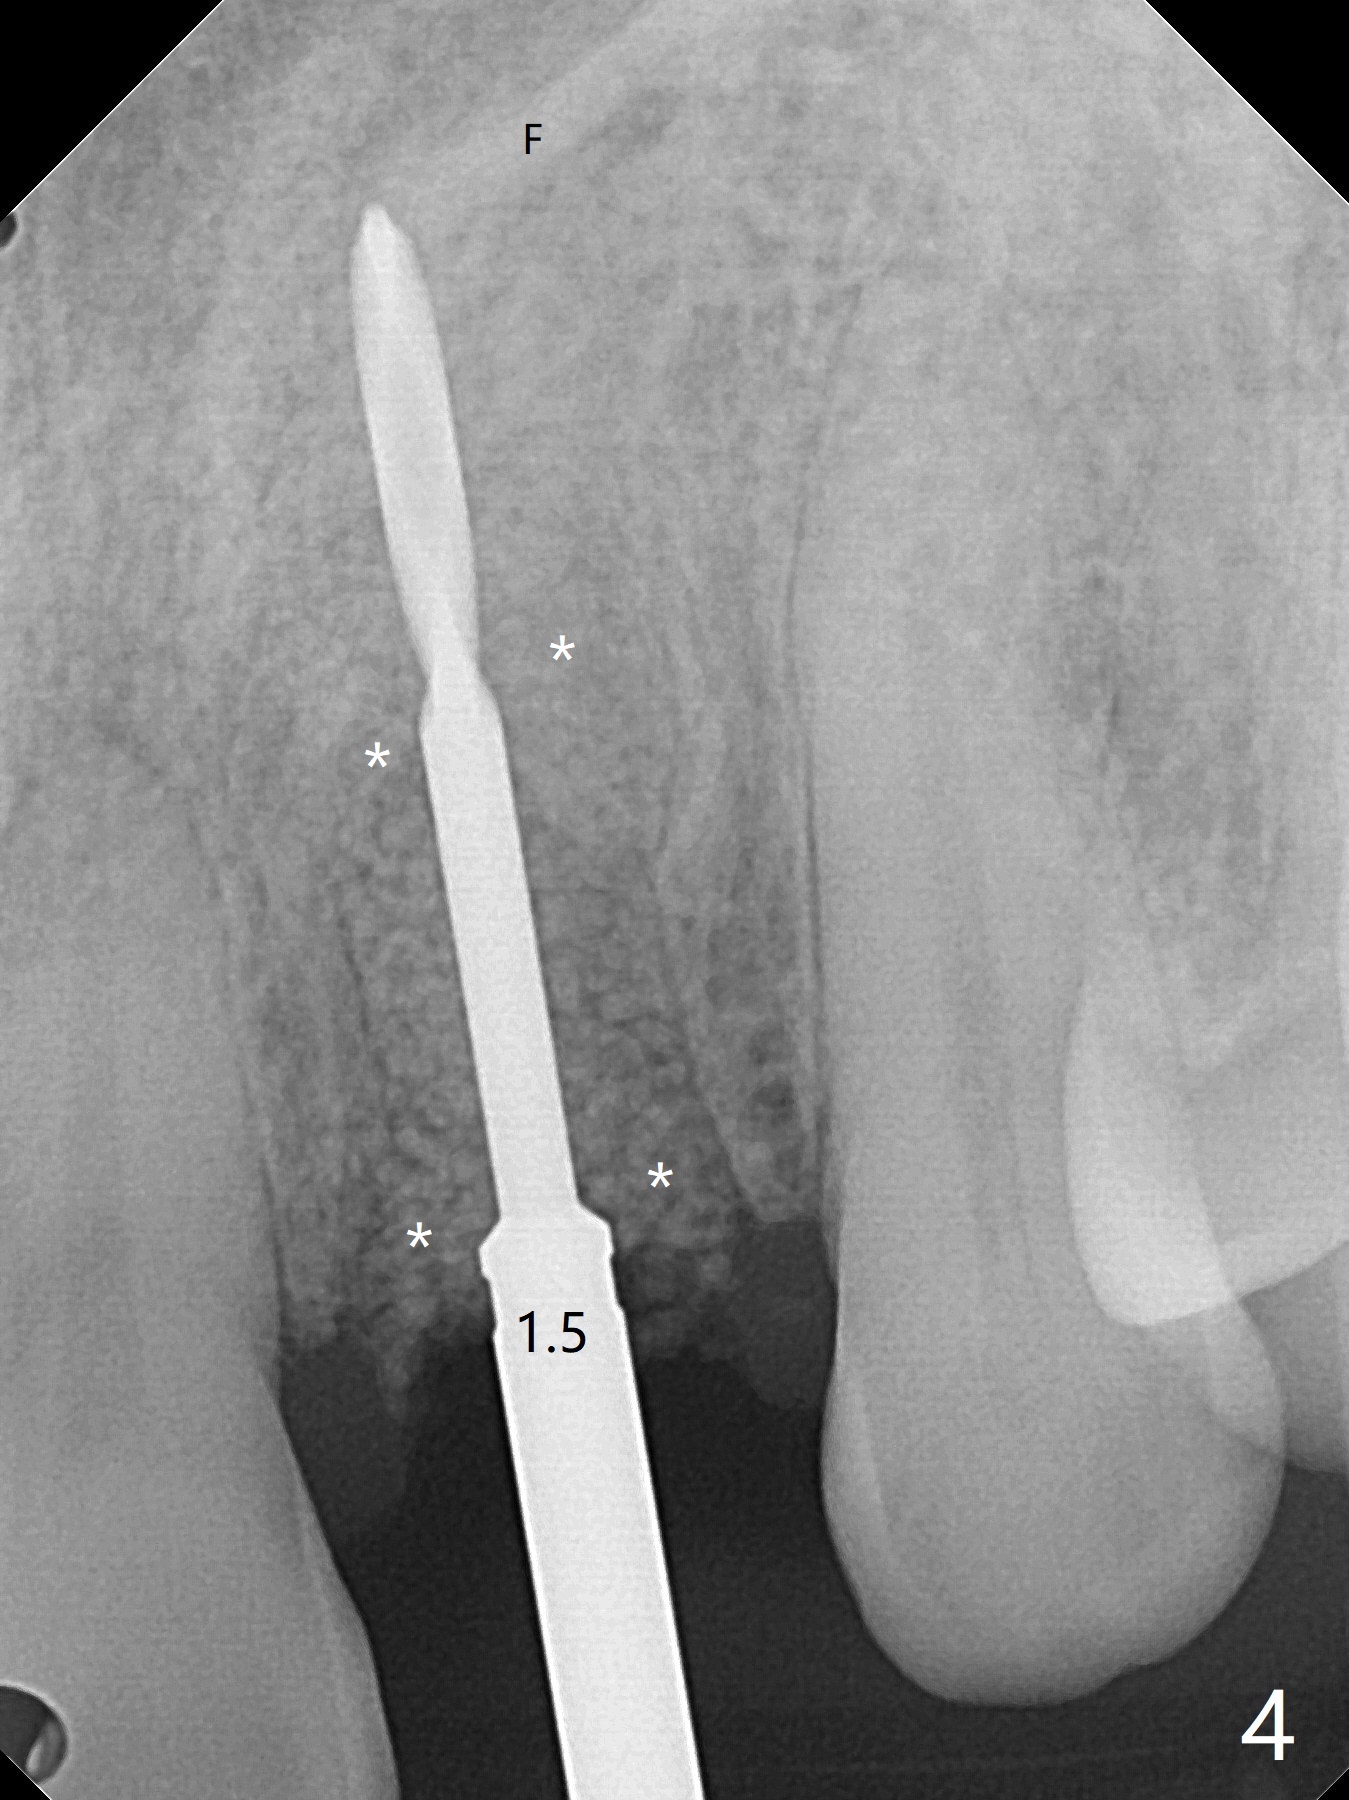

病人回来带来瘘道(图一),不过不会增加难度,病牙去除,它便自动消失。尽管颊侧骨壁完全失去,颊侧牙龈仍丰满(图二),为什么呢?第一,因为粗大牙根存在,第二两旁牙齿,牙槽骨撑着帐篷(侧切牙颊侧牙龈),第三,牙冠。为了防止术后牙龈塌陷,尽量不切开,即刻放置植体(牙根);由于前牙缘故,这次植体不能很大,所以植骨必须过度(over grafting),最后即刻制作临时牙冠,撑住牙龈。这就是所谓每个人进入角色。这个牙根有一种先天性畸形:dens in dent (图三(腭侧观):箭头)。尽管腭侧牙根畸形,腭侧骨壁吸收临床上并不严重,所以钻洞仍偏腭侧。当预定最后钻头还在钻洞时,填入大量粘性骨块(图四:*),细长植体还没有完全卡入鼻底(图五),最后好像可以(图六,七)。植体,骨粉入位(图八),最后临时牙冠出场(图九)。尽管植体小,术后一周临时牙冠仍然可以维持牙龈原有形状(emergency profile,图十:箭头(*:树脂强化牙冠固定))。图十一以不同角度显示瘘道缩小。术后三周取出有些松动的临时牙冠,骨粉虽然还没有被肉芽组织整合,但是显得正常,周围牙龈健康(图十二)。术后4个月牙龈形态正常(图十三),没有触痛;颊侧骨板轻度凹陷(图十四);骨粉仍在原位(图十五)。术后7个月骨粉仍在原位(图十五,十六,但是冠部密度减低(可能骨粉流失,需要牙周或者树脂敷料保护)),没有螺纹暴露。但是牙冠边缘暴露,说明牙龈收缩(图十七,与图十三对比),颊侧骨板仍塌陷(图十八)。插入龈线取得多个目的:修整基台边缘,取模,颊侧牙龈推向颊侧,有利于即将衬里牙冠龈缘进入龈下(图十九)。取模后牙冠边缘(图二十:<)衬里,然后修整,变窄,以便插入龈下,促进颊侧牙龈下降(图二十一,二十二)。术后8个月牙冠粘固前牙龈健康(图二十七,八),牙冠(图二十九)固位后,病人满意(图三十),咬合调整(图三十一),注意腭侧粘固粉流出通道(<)。